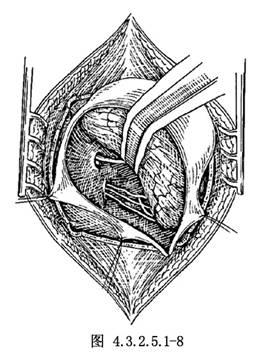

5.將腫瘤下極自第9、10、11顱神經分開,再遊離腫瘤內側面與上極。遊離上極時必須先電凝由小腦上動脈至腫瘤的分支,並予以切斷。而後將腫瘤自三叉神經分離,如腫瘤已向上突入小腦幕裂孔,小心將腫瘤向下牽拉,以便分塊切除。將腫瘤包膜牽向外側,看清位於腫瘤前下方的面神經,使面神經由腫瘤包膜遊離至靠近內耳孔處(圖4.3.2.5.1-7)。再將腫瘤由內耳孔處切斷,摘除腫瘤(圖4.3.2.5.1-8)。

殘留於內耳孔內的腫瘤組織,可用高速微型鑽磨開內耳道後壁,顯露內耳道內的腫瘤部分,將其切除,勿損傷面神經(圖4.3.2.5.1-9)。當腫瘤已從囊內基本切除後,由於其內側面與腦幹粘連緊密或嵌入腦幹內時,有時極難分離,如強行剝離,將加重腦幹損傷。手術可做到大部切除,而採用雙極電凝將腫瘤殘餘部分電凝,破壞瘤組織。囊性聽神經瘤與腦幹、顱神經的粘連較緊,界面不清,特別需要術中仔細辨認。